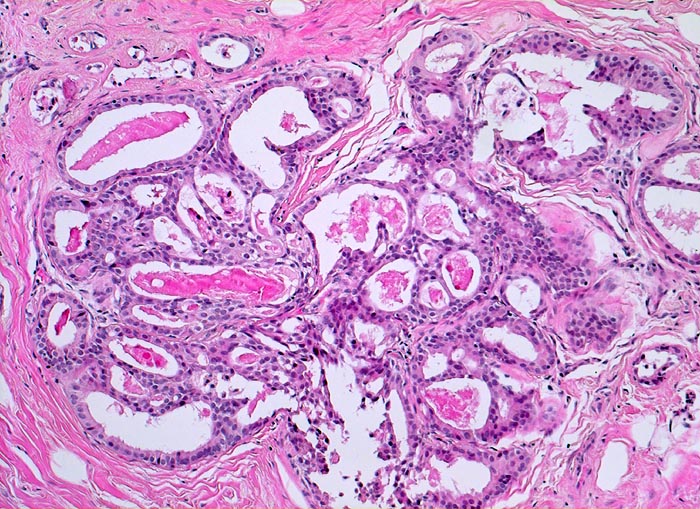

Makroskopisch bildet das mastopathisch veränderte Parenchym weisse kompakte fibröse Areale mit Einschluss von Zysten, welche oftmals eingedicktes Sekret enthalten. Neben einer Stromafibrose und zystisch ausgeweiteten Gängen mit Sekretretention findet sich oft eine unterschiedlich ausgeprägte intraduktale Proliferation von luminalen und basalen Epithelzellen. Nicht selten liegen als Begleitbefund kleine Fibroadenome, eine sklerosierende Adenose oder Gänge mit apokriner Metaplasie vor. Oftmals finden sich auch intraduktale Mikroverkalkungen. Die duktale Hyperplasie ist im Gegensatz zur atypischen Hyperplasie und zum Carcinoma in situ charakterisiert durch eine bunte, ungeordnete Proliferation ungleich grosser polygonaler bis spindeliger Zellen mit Ausbildung von schlitzförmigen Hohlräumen oder dünnen epithelialen Brücken. Die euchromatischen Kerne variieren in Grösse, Form und Lagerung. Bei paralleler Lagerung der Kerne entsteht der Eindruck eines Strömens und Fliessens der Zellen. Das duktale Carcinoma in situ ist von gutartigen intraduktalen Epithelproliferationen abzugrenzen aufgrund seiner Monomorphie (> 5185), Hyperchromasie der Zellkerne und starrer geometrischer Muster (runde scharf begrenzte wie ausgestanzte Lumina (> 5184), breite Brücken und Bögen, Mikropapillen). Eine intraduktale Epithelproliferation mit Atypie wird dann diagnostiziert, wenn nur ein Teil der Gänge oder Läppchen die typischen Veränderungen eines Carcinoma in situ zeigt. Die Abgrenzung der atypischen Hyperplasie von der Hyperplasie ohne Atypie erfolgt aufgrund qualitativer Merkmale und die Abgrenzung der Hyperplasie mit Atypie vom Carcinoma in situ aufgrund quantitativer Merkmale.

• In der Mitte rechts einige Gänge mit gewöhnlicher intraduktaler Epithelhyperplasie ohne Atypie: Polymorphe, sich überlagernde spindelige Zellen. Fliessende Anordnung der Zellen. Schlitzförmige und irregulär geformte Lumina.

• Herdförmig apokrine Metaplasie des Drüsenepithels: hochprismatische Zellen mit sehr reichlichem feingranulärem eosinophilem Zytoplasma und runden Kernen.

• Rundlicher blauvioletter Mikrokalk in den Azini benigner Drüsenläppchen.

• Kolumnarzellveränderung: erweiterte Drüsen ausgekleidet von hochprismatischem Epithel mit apikalen Nasen (snouts) gefüllt mit Sekret und teilweise assoziiert mit Mikrokalk.

• Alle Drüsen zeigen eine erhaltene äussere abgeflachte Myoepithelschicht mit hellem Zytoplasma.